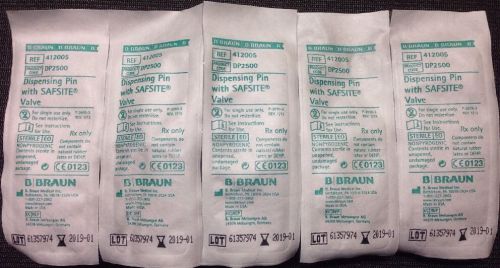

Lot Of 49 B Braun Dispensing Pin With Safsite Valve REF:412005 DP-2500